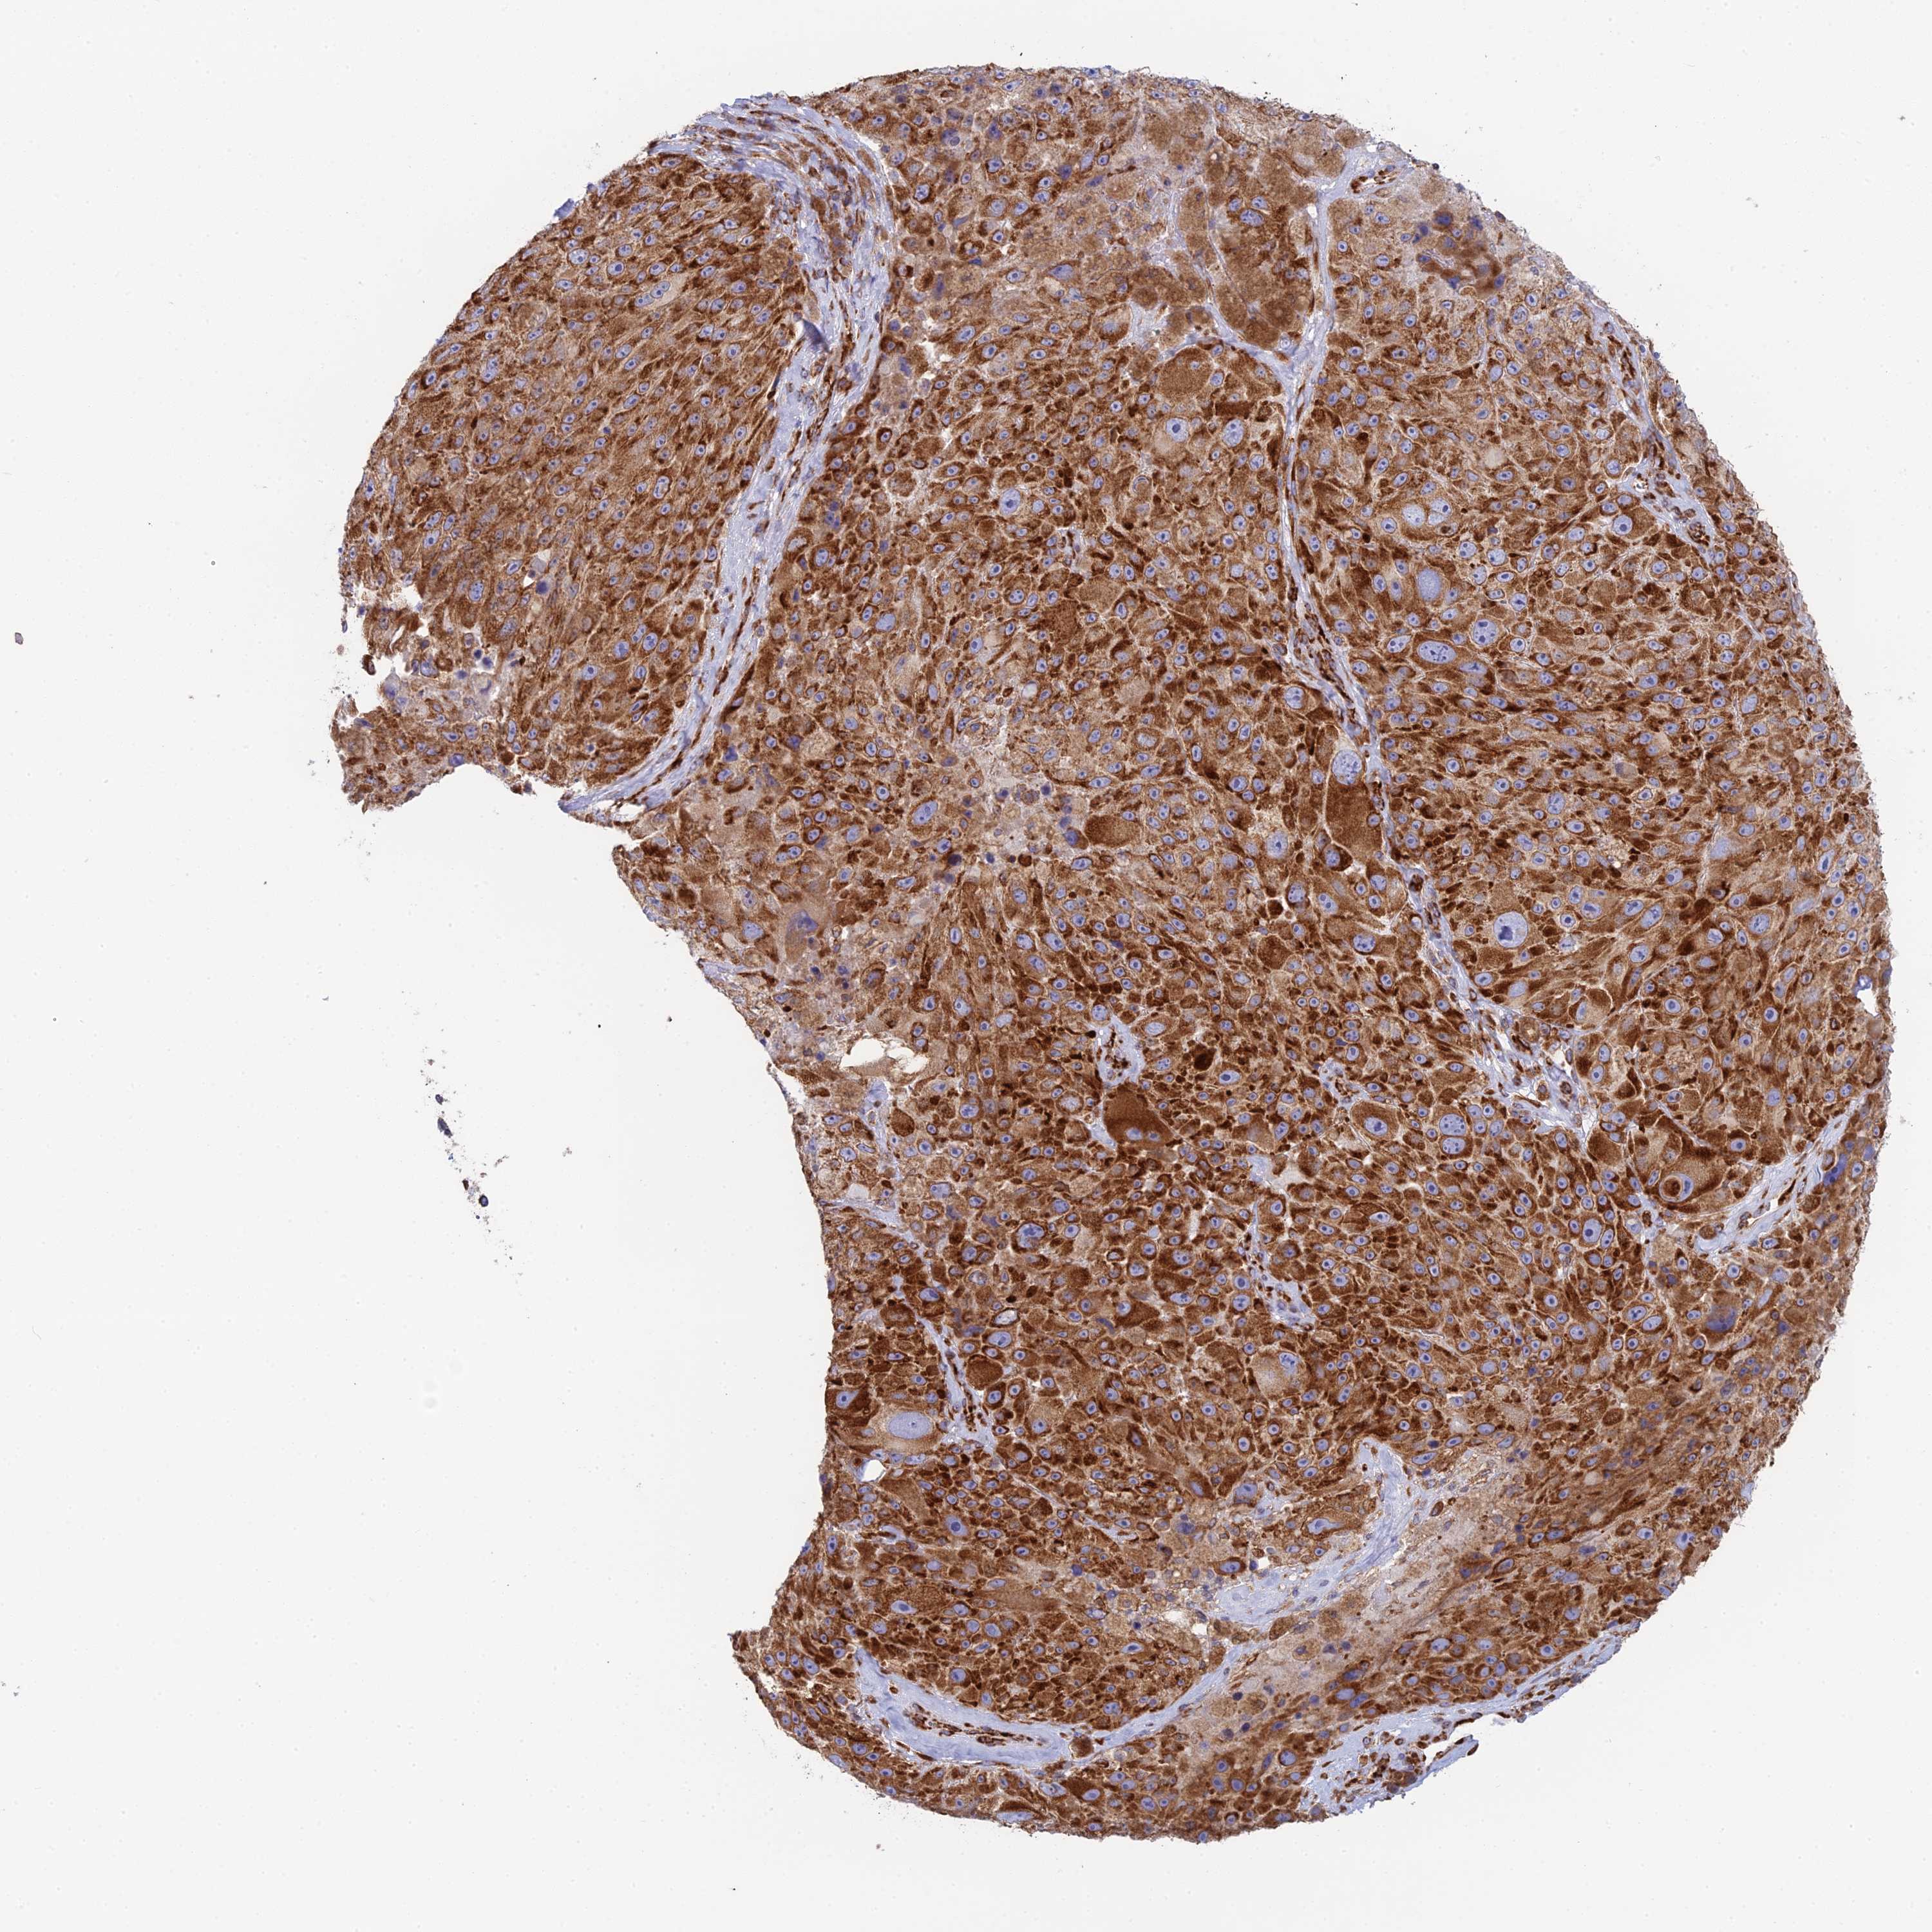

MELANOMA - Protein expressioni

A mouse-over function shows sample information and annotation data. Click on an image to view it in a full screen mode. Samples can be filtered based on level of antibody staining by selecting one or several of the following categories: high, medium, low and not detected. The assay and annotation is described here.

Note that samples used for immunohistochemistry by the Human Protein Atlas do not correspond to samples in the TCGA dataset.

Antibody stainingi

Antibody staining in the annotated cell types in the current human tissue is reported as not detected, low, medium, or high, based on conventional immunohistochemistry profiling in selected tissues. This score is based on the combination of the staining intensity and fraction of stained cells.

Each image is clickable and will lead to virtual microscopy that enables deeper exploration of all samples and also displays staining intensity scores, fraction scores and subcellular localization as well as patient and tissue information for each sample.

Antibody HPA043648

Staining

High

Medium

Low

Not detected

Intensity

Strong

Moderate

Weak

Negative

Quantity

>75%

75%-25%

<25%

None

Location

Nuclear

Cytoplasmic/membranous

Cytoplasmic/membranous,nuclear

Malignant melanoma, NOS

Malignant melanoma, Metastatic site